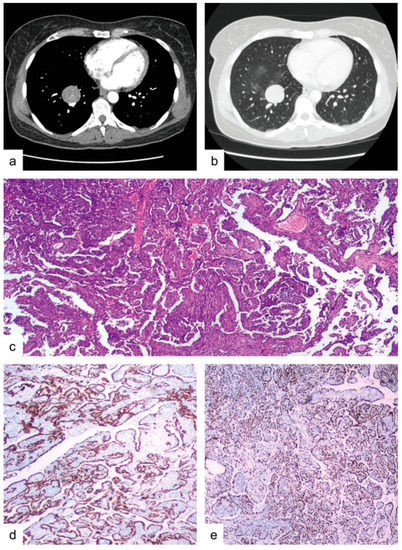

1. Introduction

2.2. Microscopic Findings

3. Case Report 2